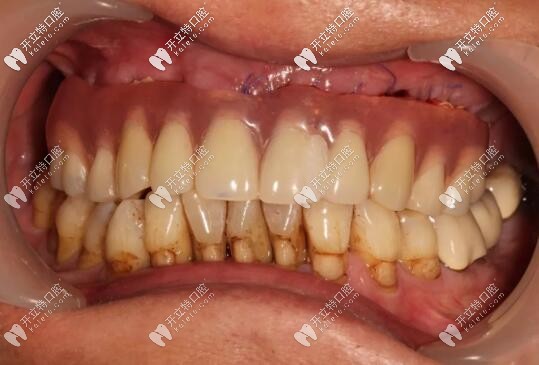

半口種植牙前

西安美奧牙科all-on-6種植牙案例

修復(fù)前

病史上頜于10年前因牙周病導(dǎo)致的牙齒缺失,曾做過可摘戴活動(dòng)義齒修復(fù)。